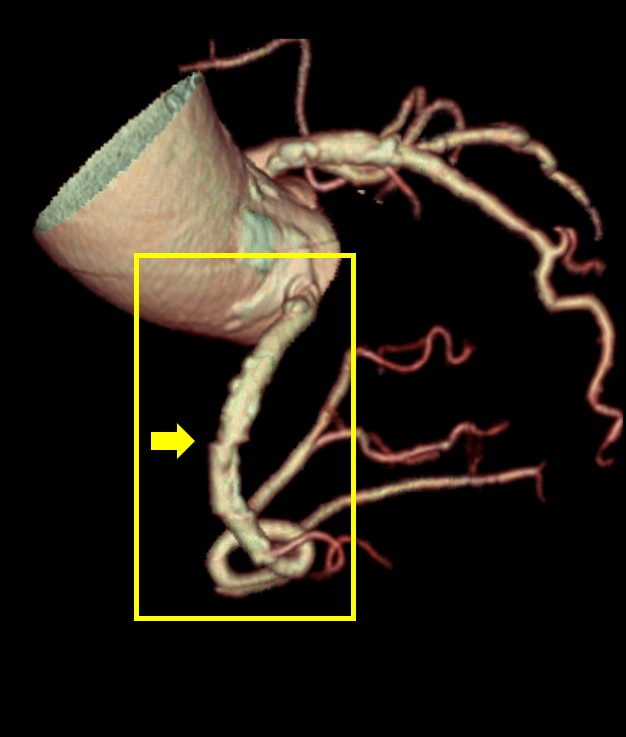

TAVI術前検査における活用例

下記の画像は、TAVI術前検査のAf症例ですが、このデータでも不整脈や石灰化があるにも関わらず弁に対して十分な画像が得られており、列数の影響を感じさせない画像が提供することができました。

循環器医師からも、「64列装置でも十分評価できているね!」と言っていただけるほど、評価が高かったことが印象的です。

Ascend_ayase04.jpgTAVI術前検査でのSSF2.0処理後の画像